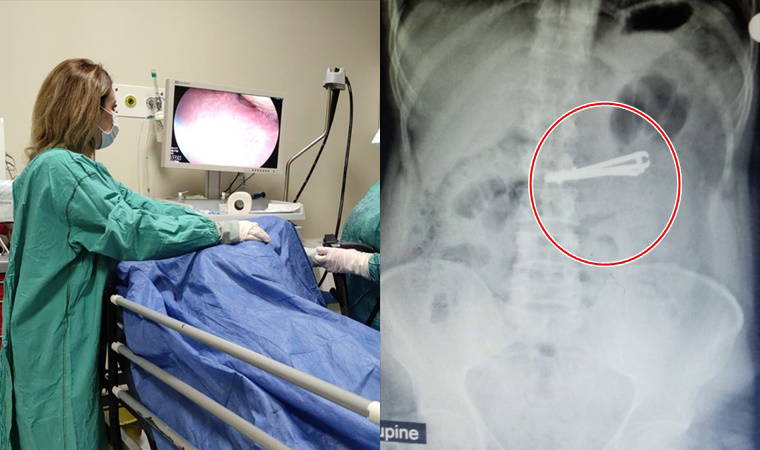

Siirt'in Kurtalan ilçesinde yaşayan ve doğuştan ağır mental retardasyon (zeka geriliği) hastası Mutih Akurt (42), elindeki tırnak makasını yuttu.

Akurt, yakınlarının durumu fark etmesi üzerine kaldırıldığı Kurtalan Devlet Hastanesinde yapılan tetkiklerin ardından Siirt Eğitim ve Araştırma Hastanesine sevk edildi. Hastanın midesindeki tırnak makası, Genel Cerrahi Uzmanı Dr. Yasemin Küçük'ün yaptığı endoskopiyle çıkarıldı.

Sağlığına kavuşan Akurt, daha sonra taburcu edildi.